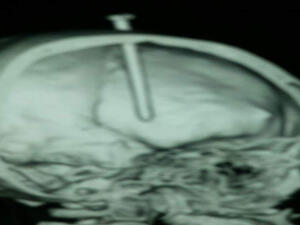

صورة بالاشعة للمسمار في الرأس

10 فبراير 2016 - 07:37 GMT

بالصور.. سوداني دق مسمار برأسه.. والسبب